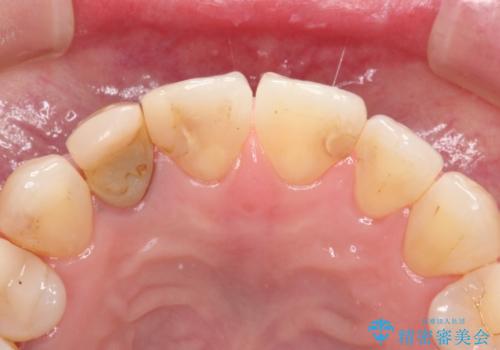

前歯が痛い。根管治療~オールセラミッククラウン

- 前歯が痛いことを主訴に来院されました。

根管治療を行った後、オールセラミッククラウン(エクセレント)にて治療を行いました。